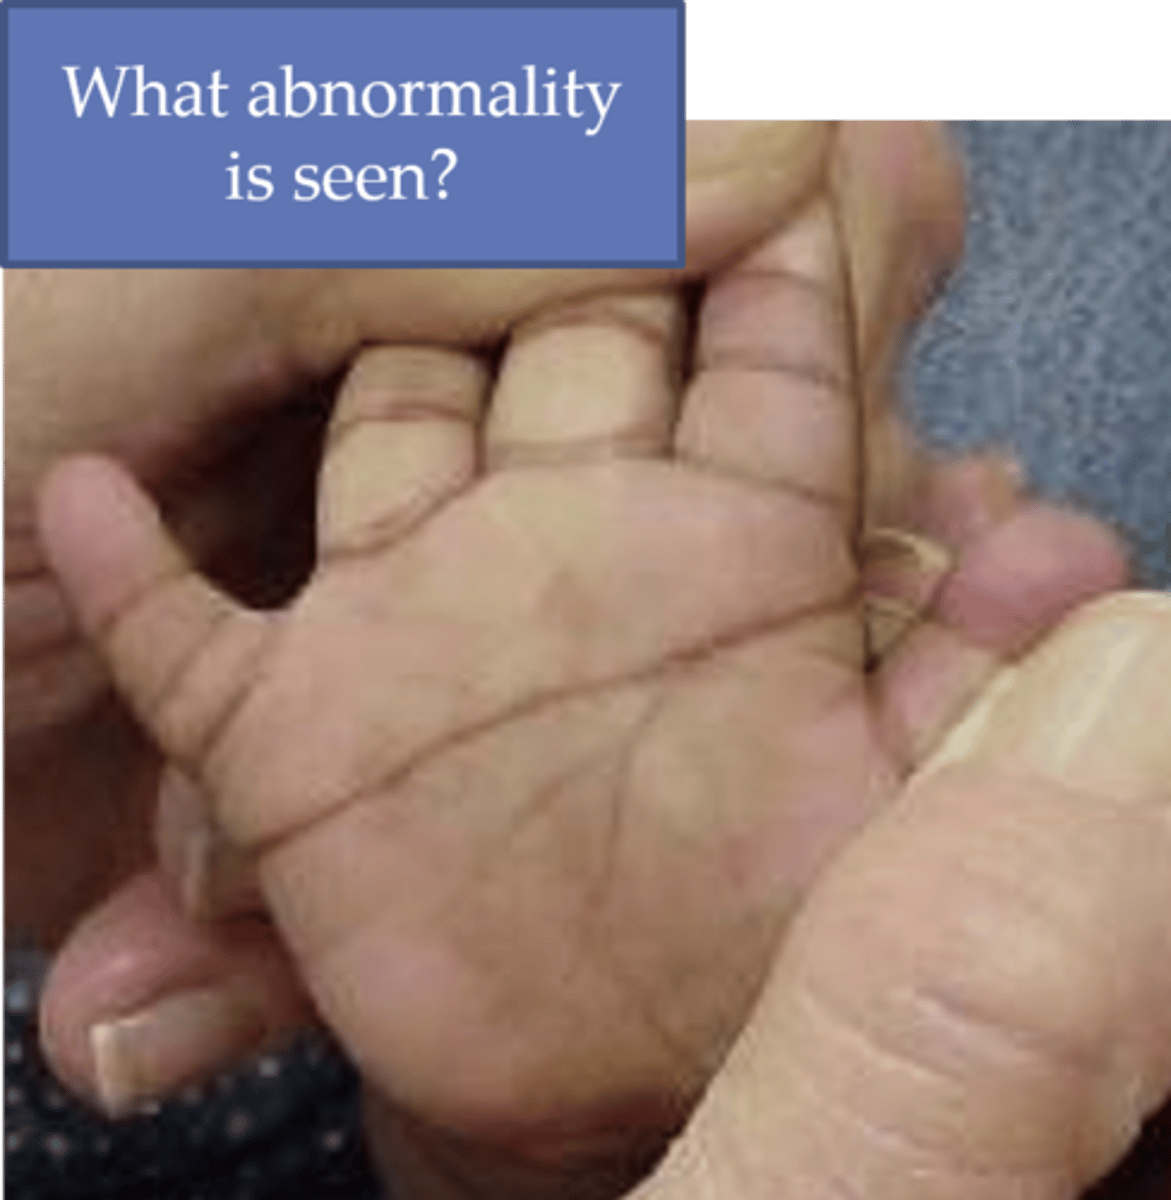

Single palmar crease, epicanthal folds, excess skin at neck, protruding tongue, upslanting palpebral fissures, ostium PRIMUM ASD (inferior part), duodenal atresia

Down syndrome (trisomy 21), VSD > 50%